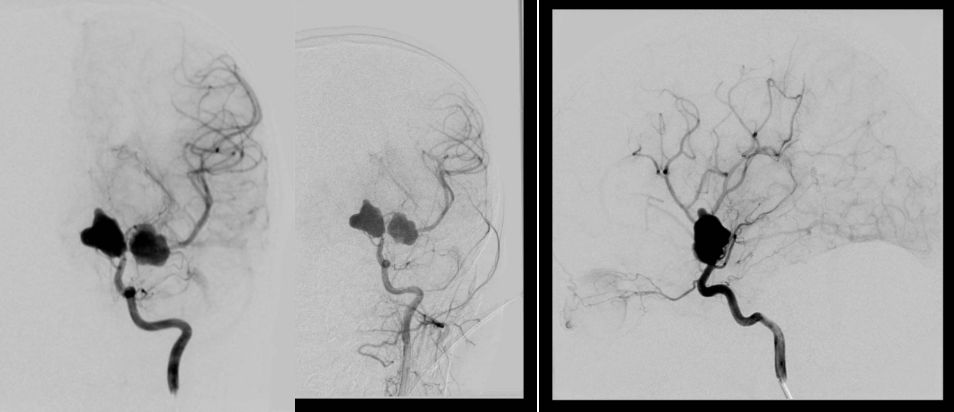

进一步DSA检查提示:左侧颈内动脉末端,大脑中动脉起始段两枚异常瘤体影,形态不规则,大小约12.1mm*15.3mm,13.6mm*12.2mm,左侧A1显示欠佳,考虑左侧大脑中动脉起始部多发动脉瘤。(图3)

![]()

图3. 左侧颈内动脉造影,显示左颈内动脉末端,A1,M1起始处两个动脉瘤